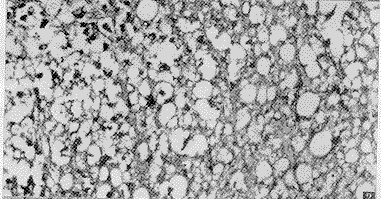

7.1 mm7 mW/cm2治疗组与损伤组相比,神经元病理改变程度明显减轻,神经元脱失较损伤组减少。脊髓灰、白质结构较损伤组完整,神经纤维粗细不等,未见明显碎裂,神经纤维肿胀减轻(图3)。尼氏染色下见神经元尼氏体较损伤组保存好。而4.9 mm7 mW/cm2组、8.9 mm7 mW/cm2组与损伤组比较无显著差异。

图3 7.1mm-7.mW/cm2组:神经元数量较损伤组多,神经元改变较损伤组轻 HE×200